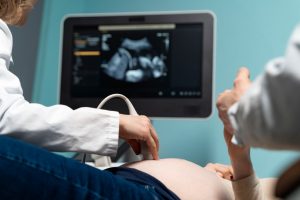

USG adalah prosedur medis yang menggunakan gelombang suara berfrekuensi tinggi untuk menghasilkan gambar organ tubuh, termasuk janin di dalam rahim. Teknologi ini memungkinkan dokter dan Sobat Sehat melihat kondisi kesehatan ibu dan bayi secara real-time. Dengan alat ini, Sobat Sehat tidak hanya bisa memantau pertumbuhan janin, tetapi juga mengidentifikasi potensi masalah kesehatan lebih awal.

Keuntungan dari USG tidak hanya bersifat medis, tetapi juga emosional. Melihat wajah mungil janin untuk pertama kalinya melalui layar USG adalah pengalaman luar biasa yang memperkuat ikatan emosional antara ibu dan bayi.

- Memantau pertumbuhan dan perkembangan janin, USG membantu dokter memantau perkembangan janin secara rinci. Mulai dari ukuran tubuh, berat badan, hingga perkembangan organ, semuanya dapat dipantau untuk memastikan bayi tumbuh sesuai usia kehamilan. Sobat Sehat tentu merasa lebih tenang mengetahui bayi tumbuh dengan baik.

- Mendeteksi kelainan atau komplikasi kehamilan, teknologi USG memungkinkan dokter mendeteksi kelainan sejak dini, seperti cacat lahir, kehamilan ektopik, atau masalah pada plasenta. Deteksi dini ini memungkinkan dokter mengambil tindakan cepat dan tepat untuk menghindari komplikasi lebih lanjut.

- Mengetahui posisi janin, menjelang persalinan, mengetahui posisi janin sangat penting. Posisi kepala di bawah adalah yang paling ideal untuk melahirkan secara normal. Jika janin berada dalam posisi sungsang atau melintang, Sobat Sehat bisa berkonsultasi dengan dokter untuk opsi terbaik.

- Mengidentifikasi jumlah air ketuban, melalui USG, dokter dapat memastikan bahwa jumlah air ketuban cukup untuk mendukung perkembangan janin. Jika terlalu sedikit atau terlalu banyak, langkah medis dapat diambil untuk menjaga kesehatan ibu dan bayi.